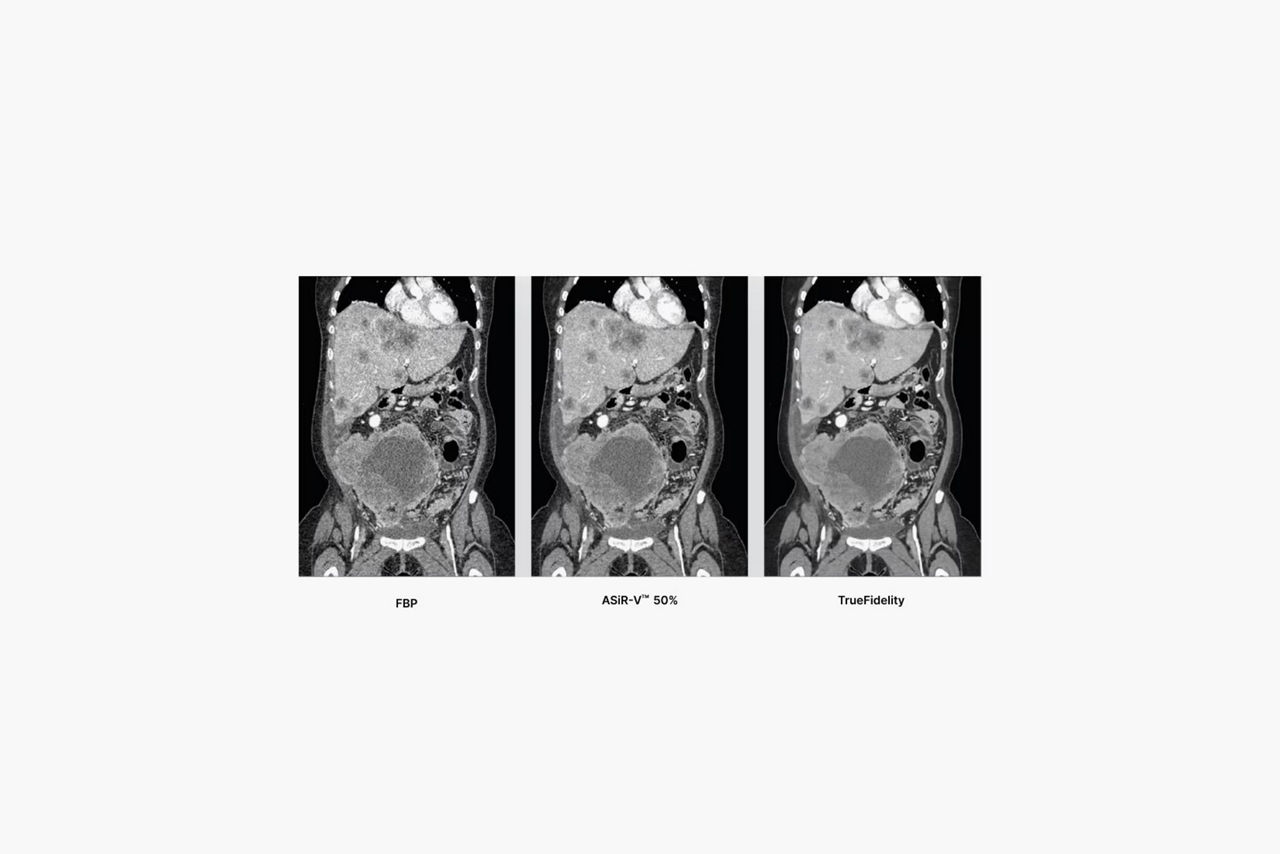

TrueFidelity

Deep-learning based image reconstruction with Revolution EVO Gen 3 CT

TrueFidelity

Deep-learning based image reconstruction with Revolution EVO Gen 3 CT

For years, low dose was the benchmark for image quality by which every CT image was held. We helped set the standard for low-dose imaging back in 2008 by introducing the industry’s first iterative reconstruction technology capable of lowering dose. Over the years, the benchmark has changed. While dose is still important, radiologists are looking for an image texture reminiscent of the text-book quality images they studied in medical school.

Take your CT experience even further on a system designed for TrueFidelity, our latest innovation in CT image reconstruction technology that uses a deep-learning based reconstruction engine to combine the low-dose CT you expect with the image texture you want.